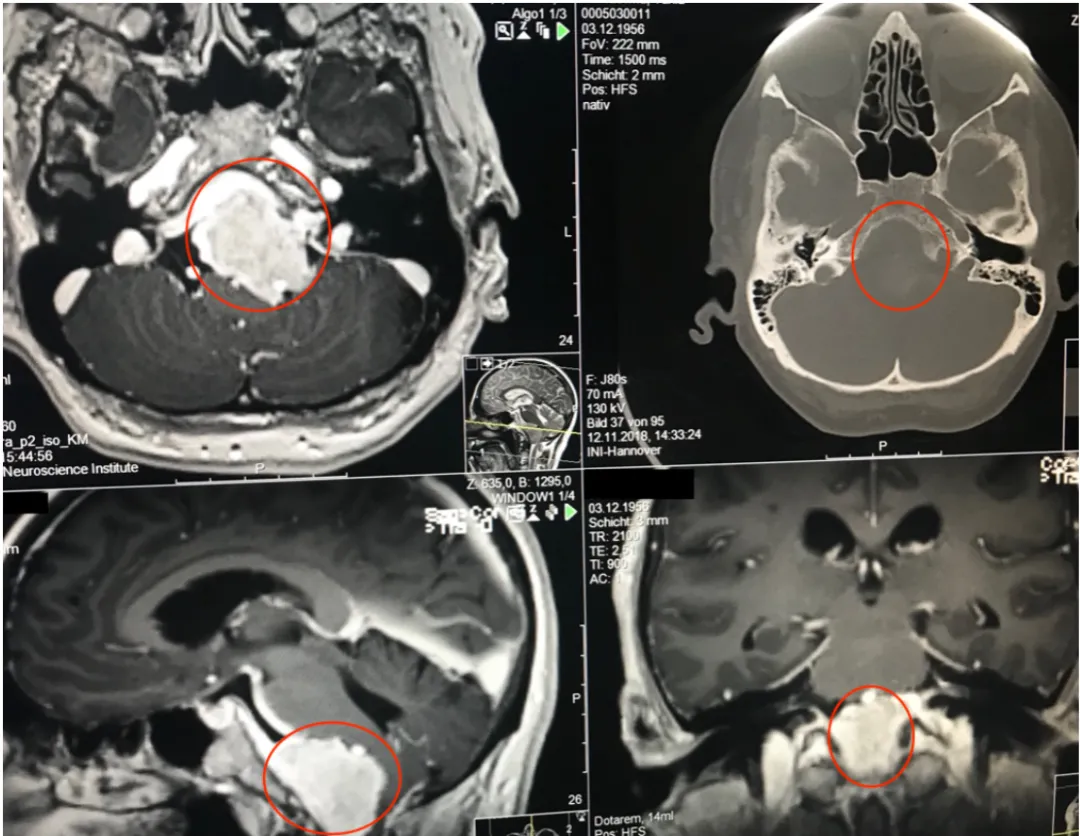

40+岁,女性,持续1年多的症状加重——相继出现头痛、复视、肢体无力、吞咽困难等,当地医院诊断为巨大岩斜区脑膜瘤,辗转多地医院均告知手术风险大,术后并发症风险发生率高,后寻求INC巴特朗菲教授手术治疗,肿瘤近全切,无相关手术并发症。

术前MR示:岩斜区巨大脑膜瘤,压迫脑干、颅神经,侵犯基底动脉等

术后MR显示:肿瘤近全切除,术后未见脑血肿、脑水肿,神经血管、脑干等组织保护完好